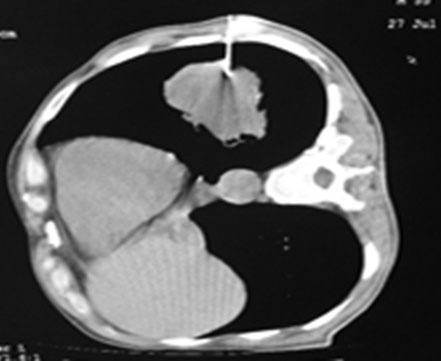

CT guided lung biopsy